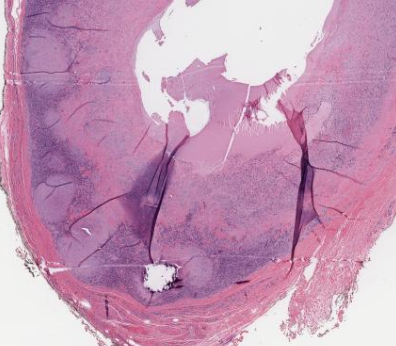

Ossifying fibromyxoid tumor of soft parts

*shell of bone present

*fibromyxoid matrix